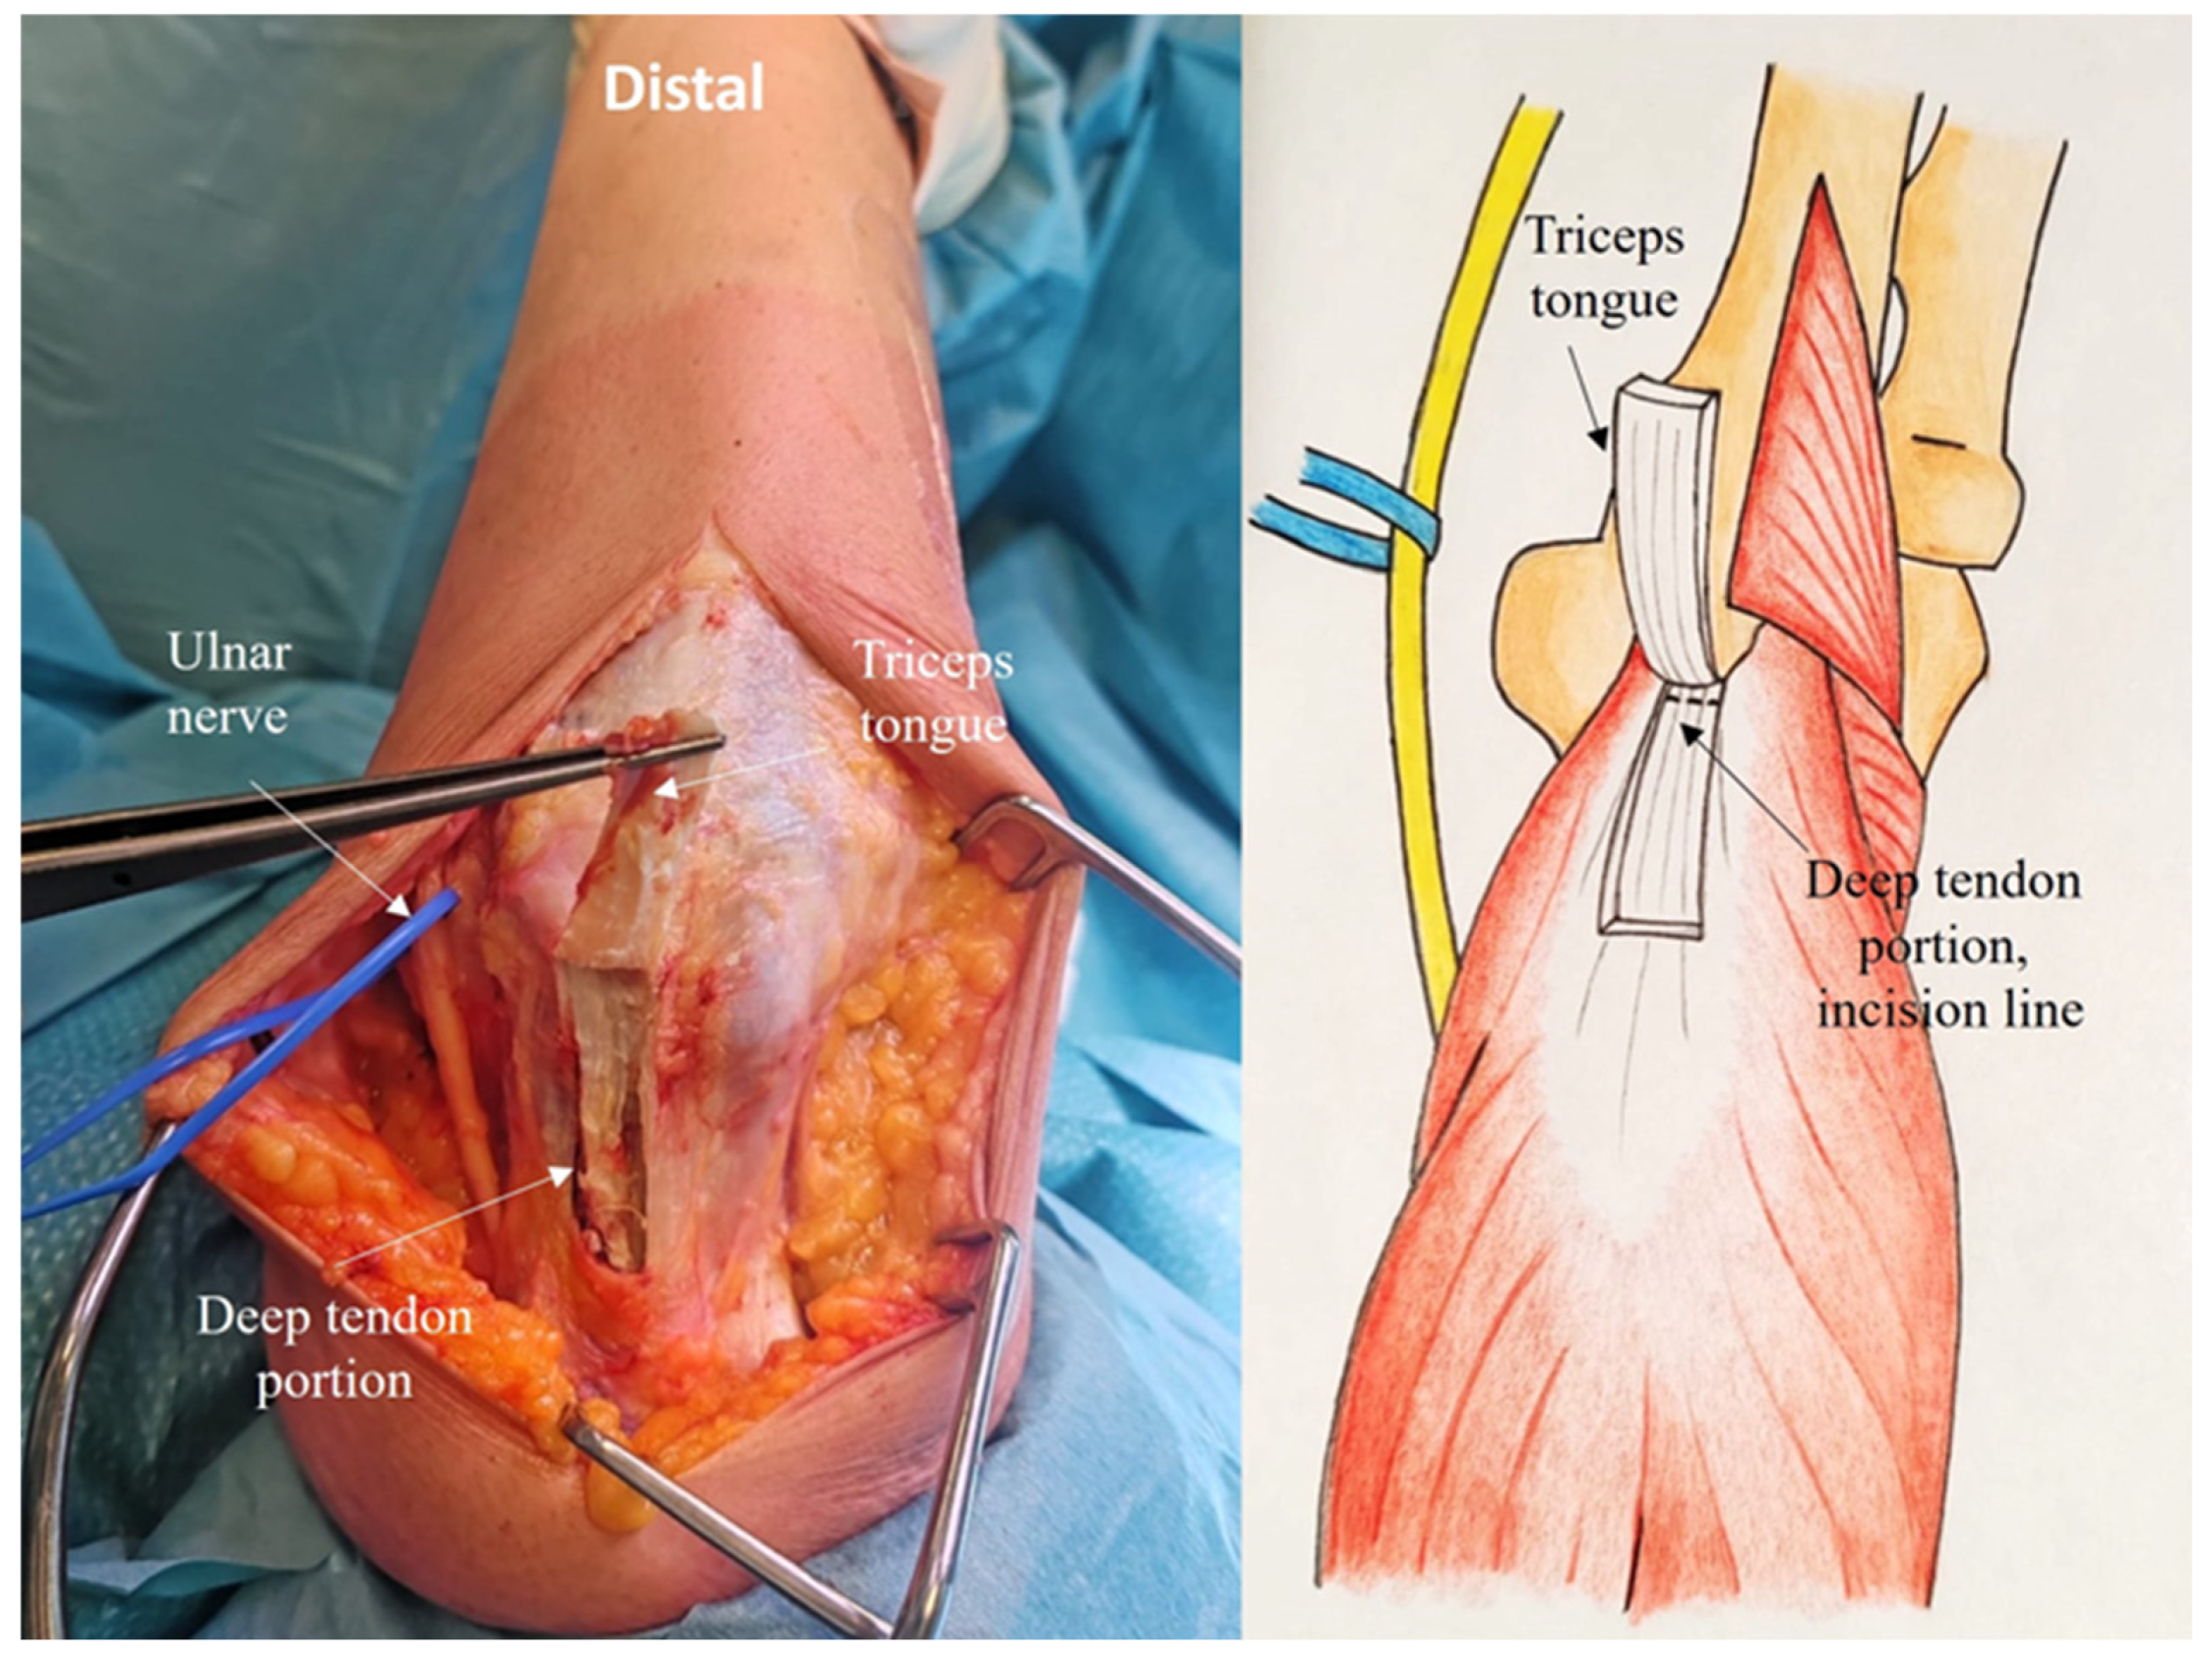

2.4. Development of the ARTT Approach